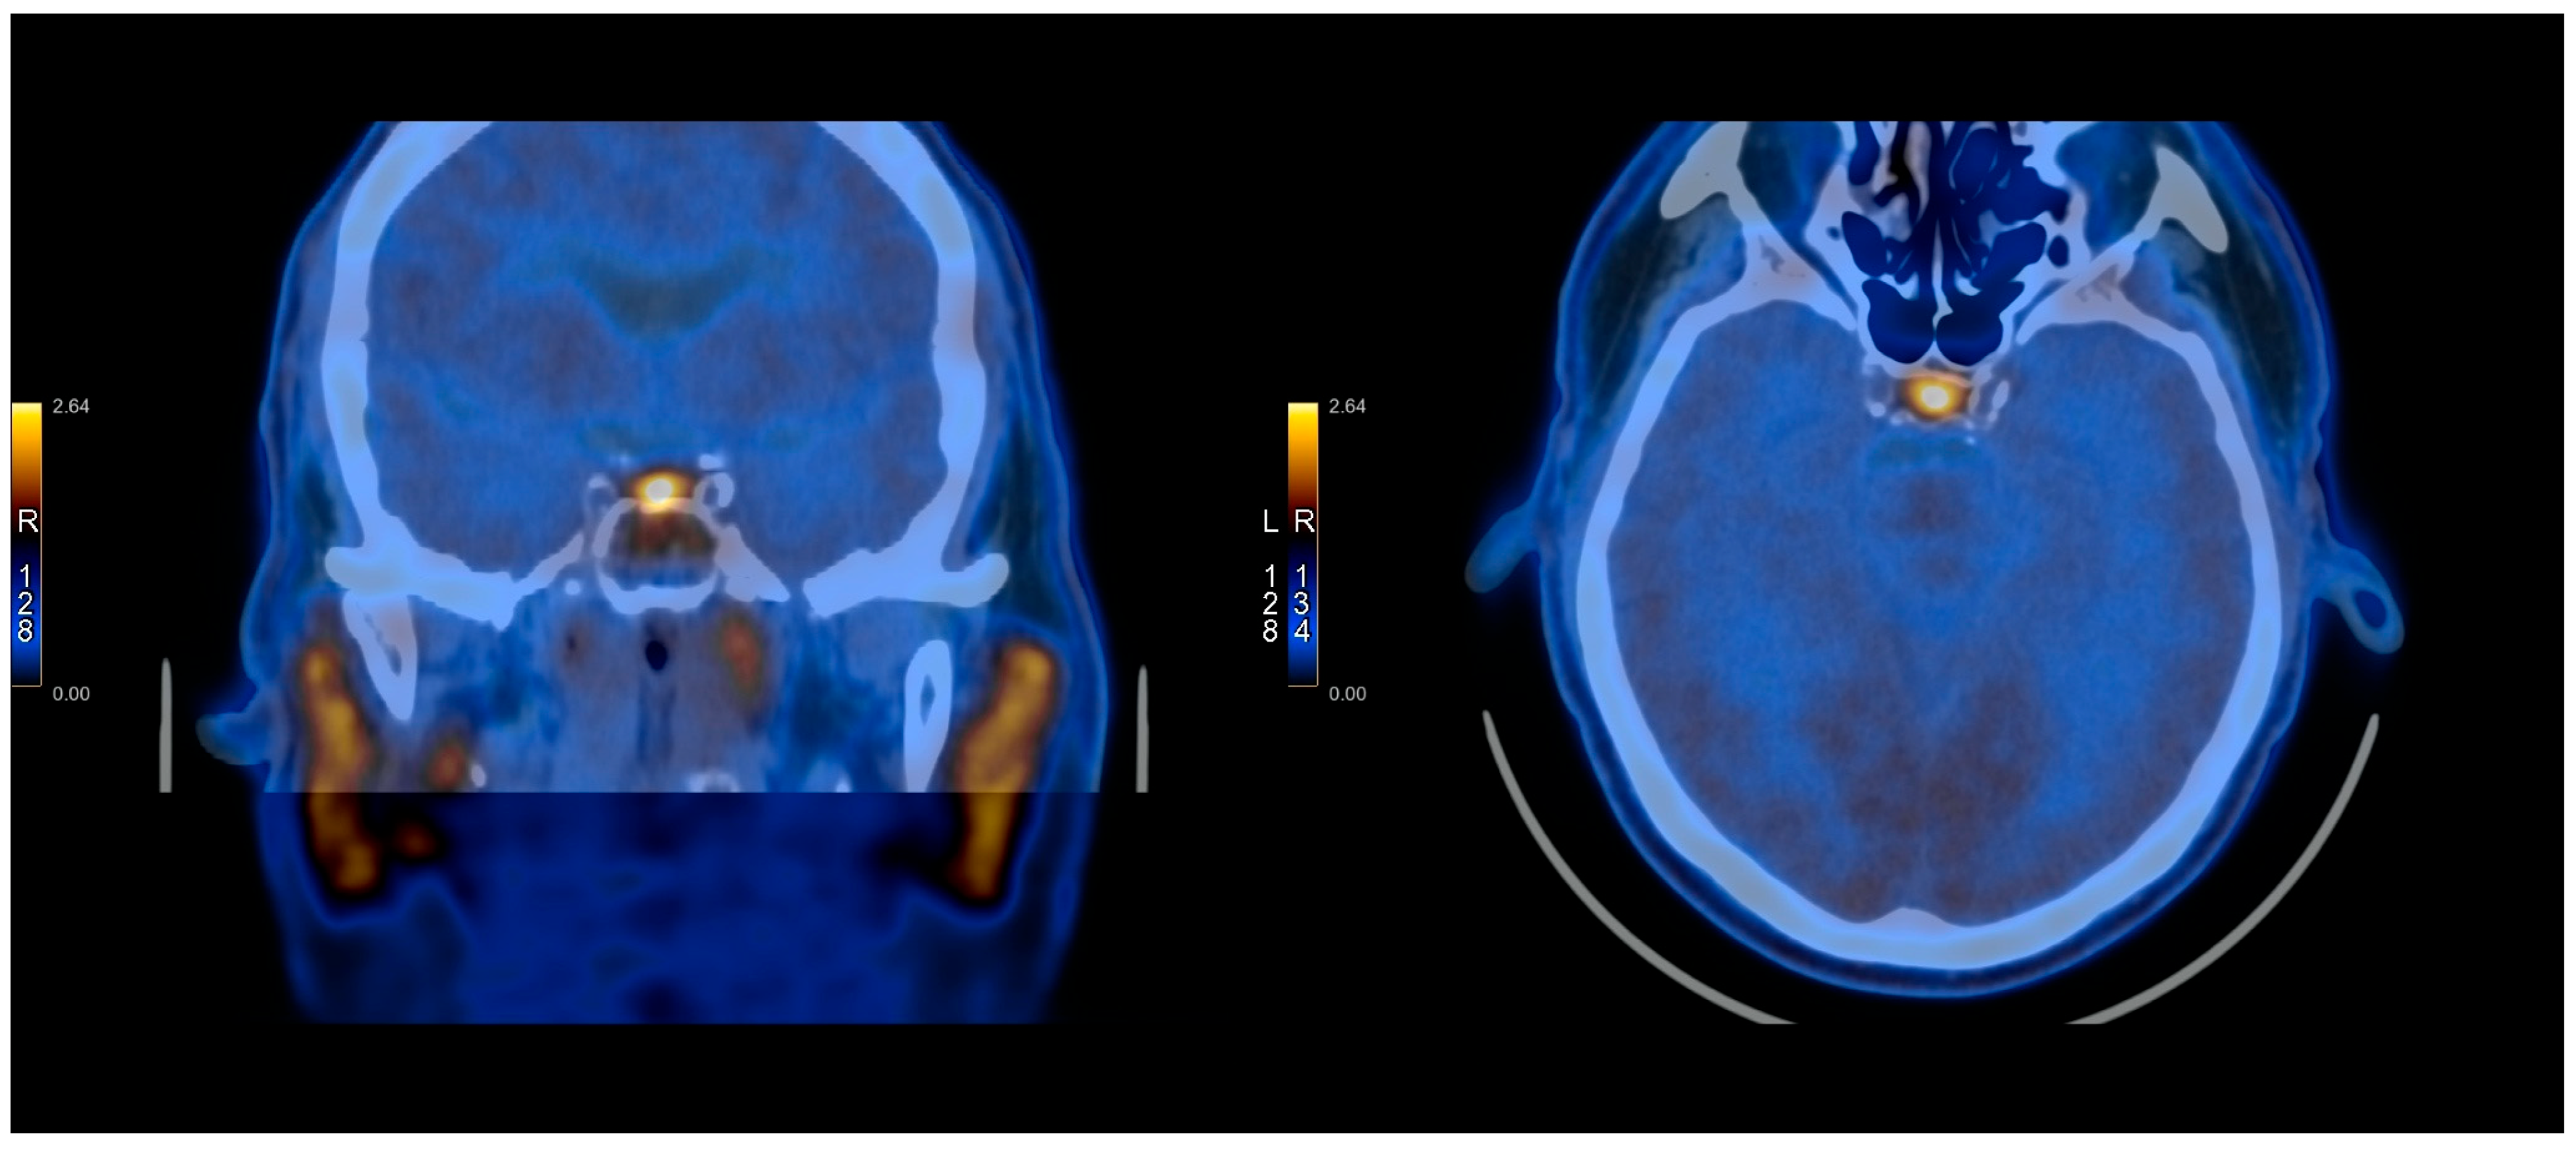

2.3. PET Protocol

2.4. Methionine Protocol